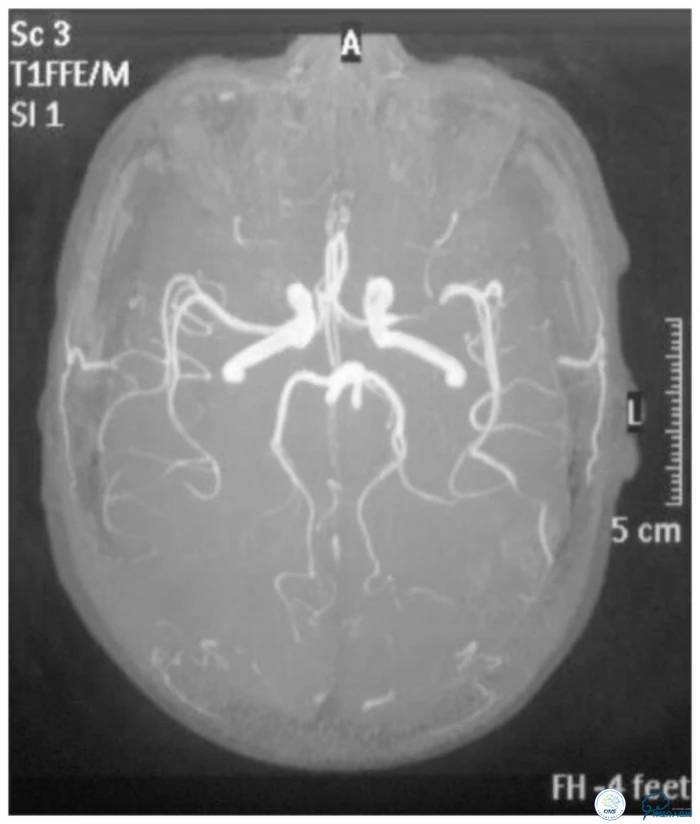

CTA:左大脑中动脉水平段狭窄(图5)。

图5